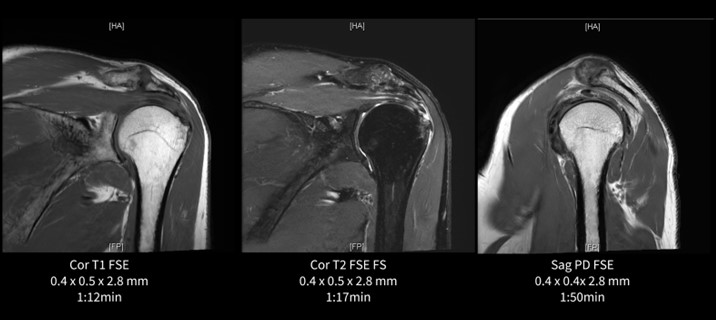

肩関節(棘状筋腱部分断裂疑い)

肩はGEM Flex Coilで撮像している。従来はPROPELLERで撮像していたが、アップグレードをきっかけにAIR™ Recon DLが併用できる2D FSEの撮像法に変更した。撮像時間は短縮され、空間分解能の向上により棘上筋腱の断裂部分や大結節の軽度陥凹と骨髄浮腫も明瞭に観察することができる。呼吸や体動の影響が大きい場合は従来通りPROPELLERで撮像しているが、患者さんの違いによる対応の幅が広がったこともAIR™ Recon DLの恩恵と考える。

図4.肩関節(棘上筋腱部分断裂疑い)